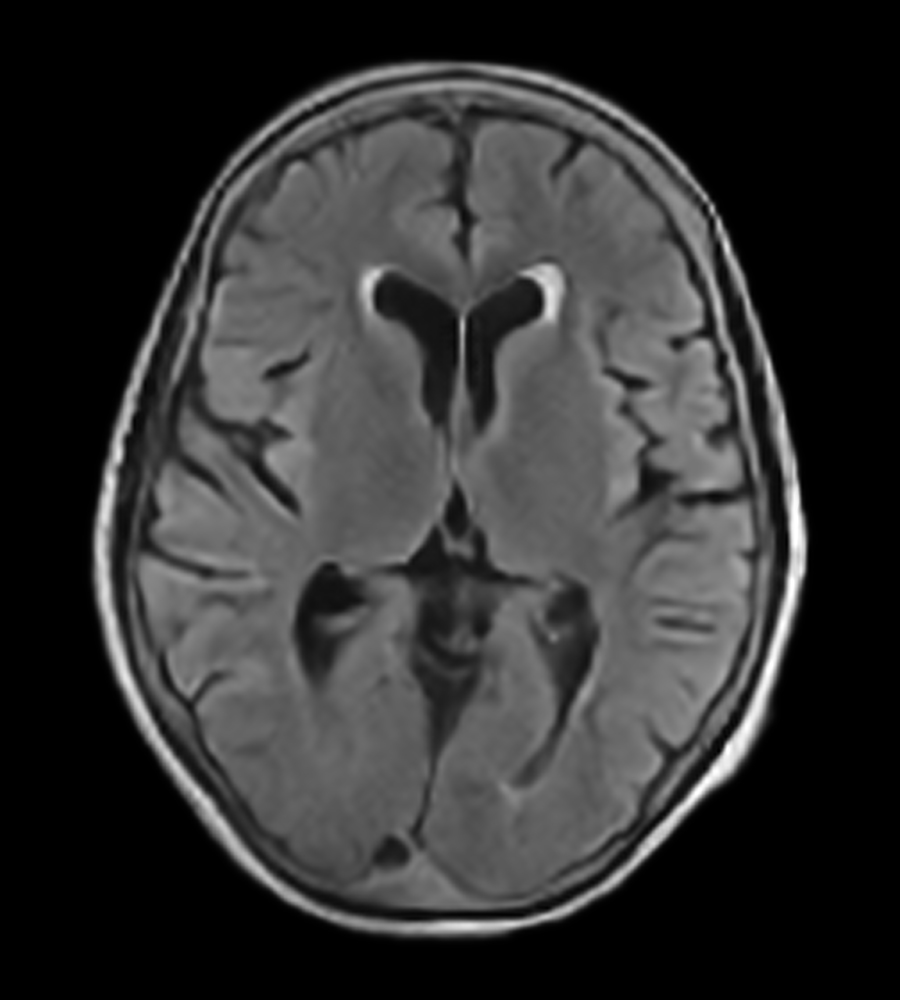

Clinical Images

Clinical Case Types: Headache, Migraine, Multiple Sclerosis, Microvascular Disease, and Tumor Routine Follow-up.

Microvascular Disease